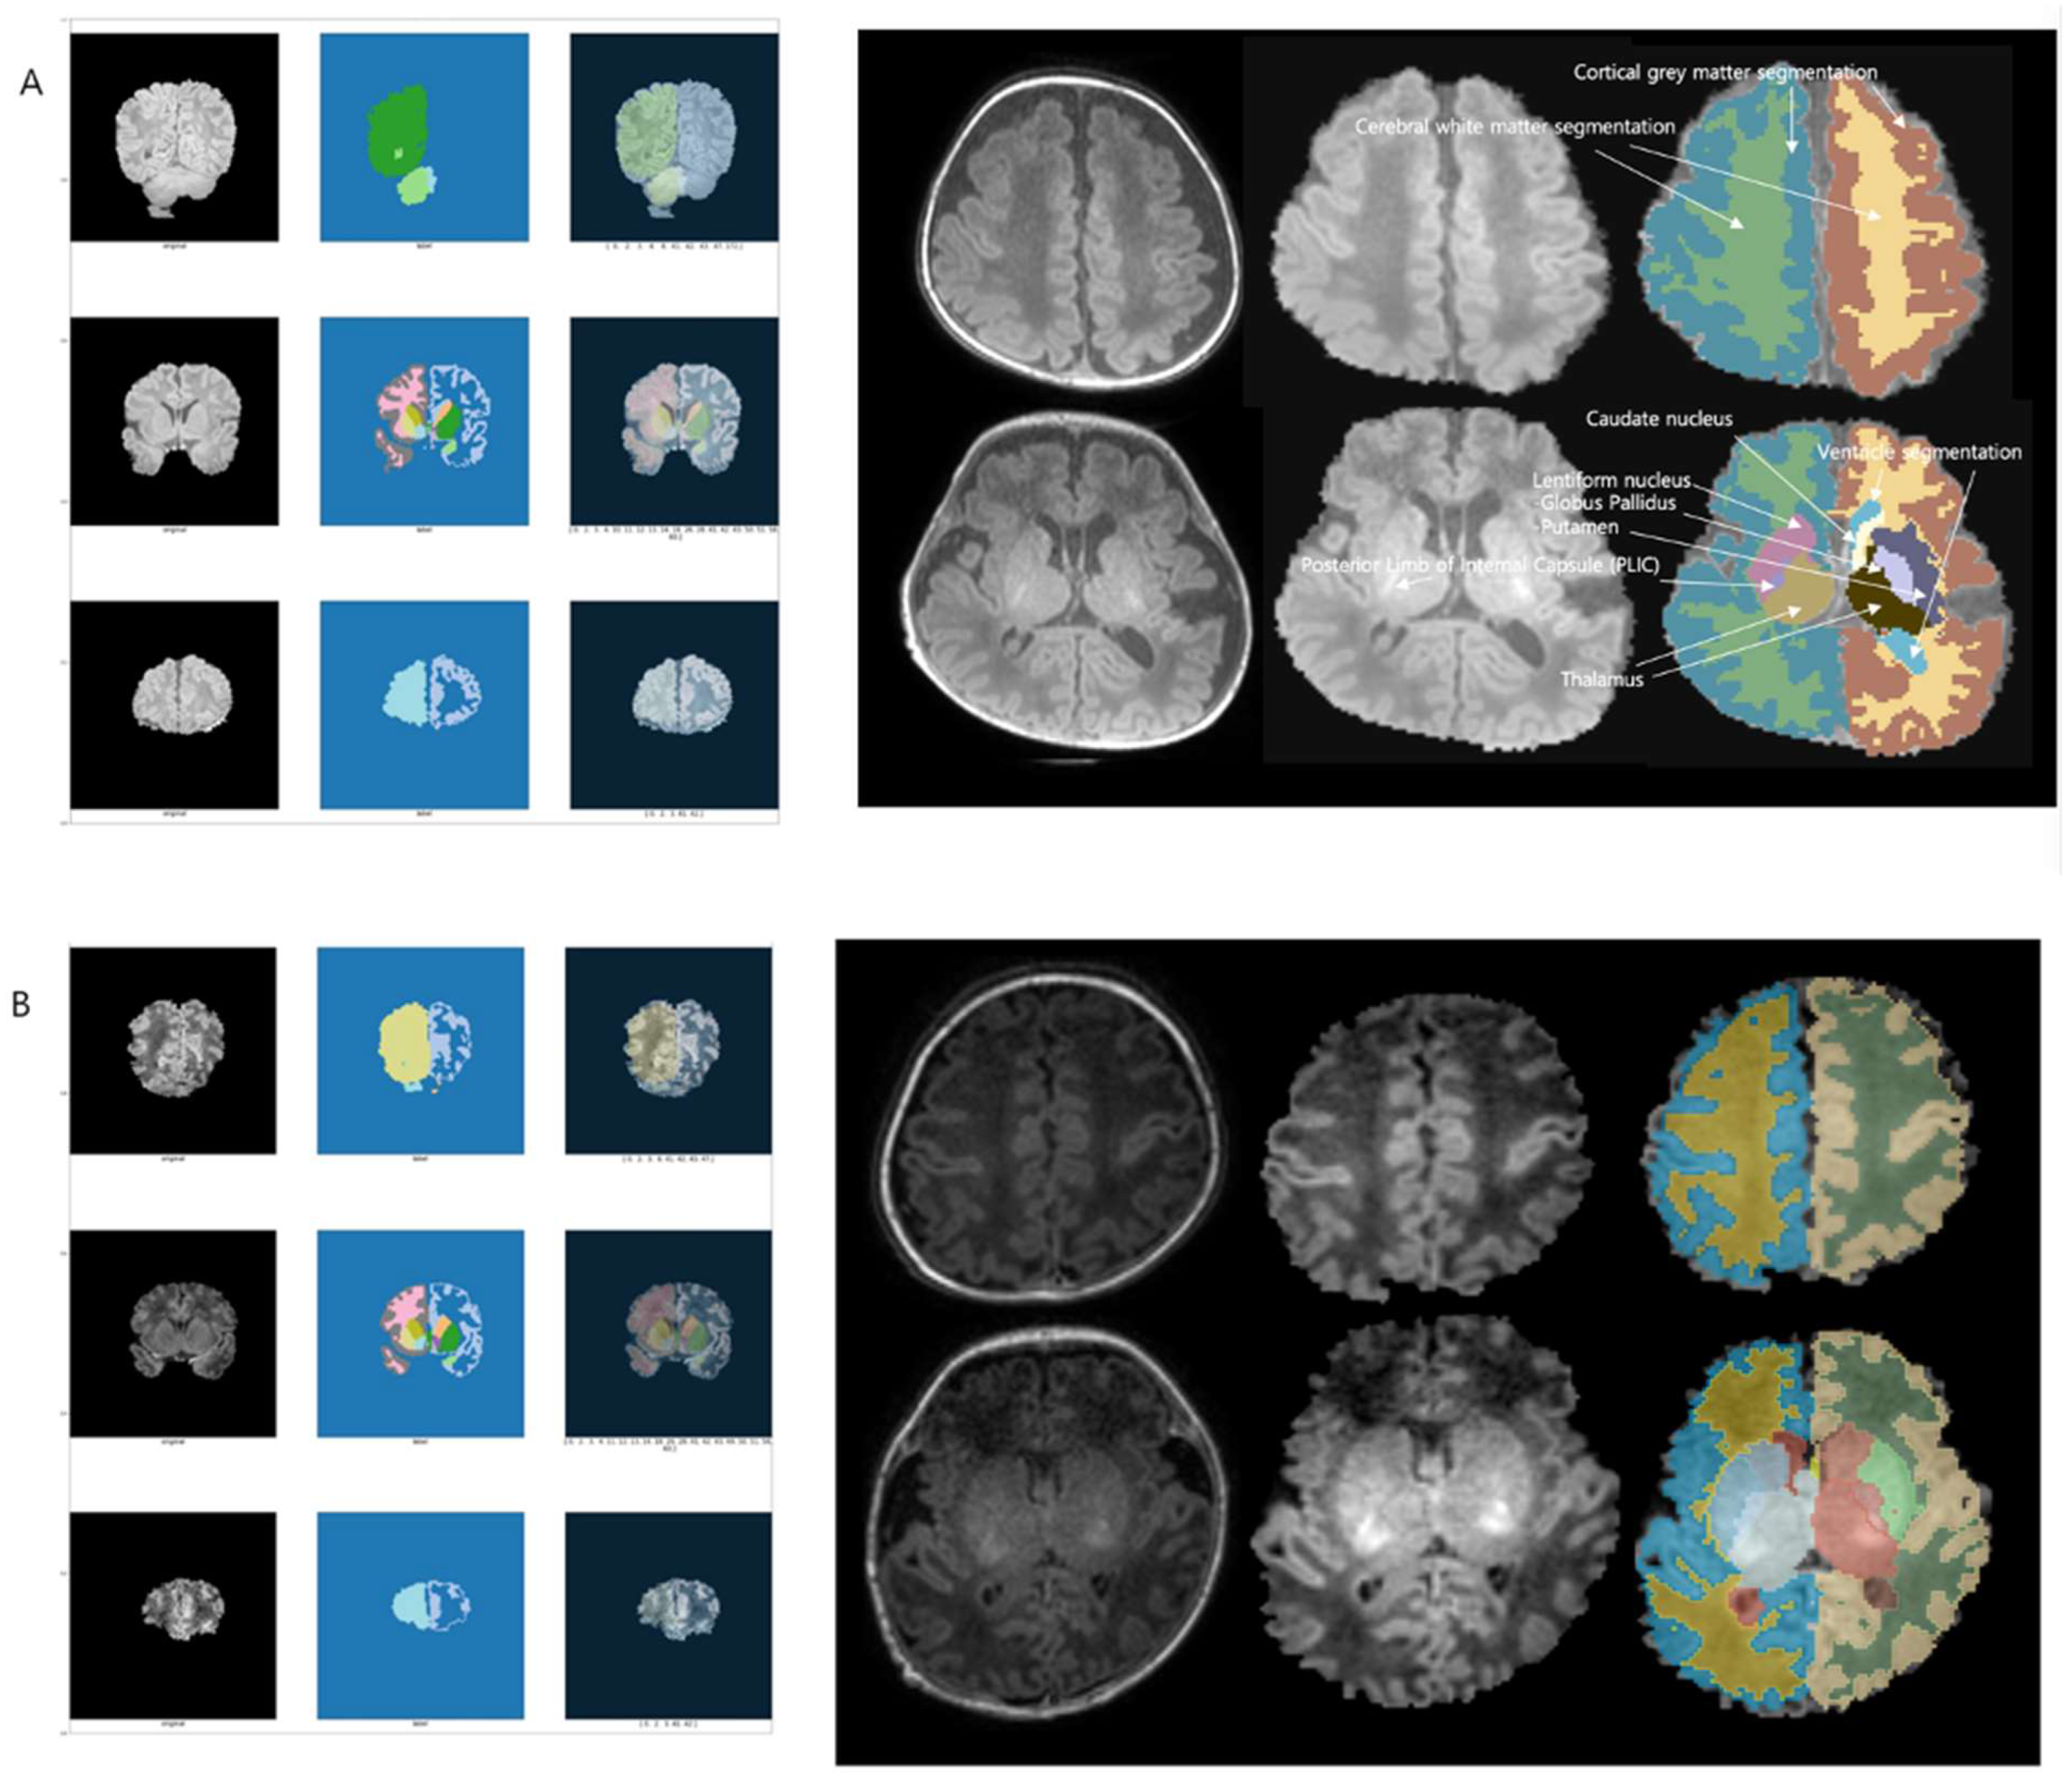

2.4. Image Processing and Analysis